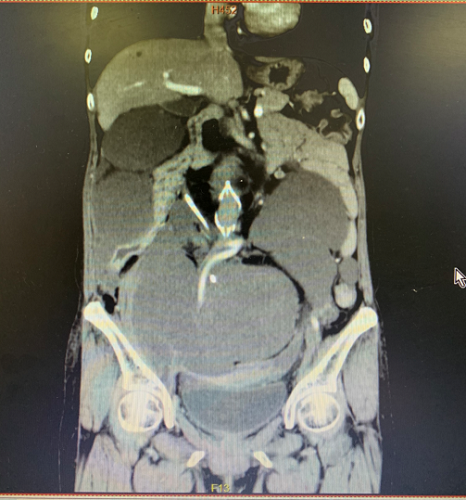

(患者的增强CT)

“求求您,让我看看儿子上大学吧!”——患者于某某,女,51岁。2004年,怀胎十月的她剖宫产,顺利生下了一个胖小子,伴着喜悦的同时,一个噩耗也传来,术中诊断了腹膜后黏液性脂肪肉瘤,也做了第一次腹膜后黏液性脂肪肉瘤手术。谁知道,这才仅仅是开始噩梦的开始!腹膜后黏液性脂肪肉瘤,它是一个奇怪的肿瘤,低度恶性的肿瘤,不易发生血行和淋巴转移,以腹腔内转移为主,但最主要特点是极易复发,多次手术可以延长患者生存率。正因为如此,15年间患者之后做了9次手术,小肠只剩不足2m,右侧肾脏因压迫梗阻已无功能,腔静脉也因癌栓放置了血管滤网。第9次肿瘤复发时,腹腔粘已连极其严重,肿瘤也已经压迫双侧输尿管,侵犯腹壁、膀胱,肿瘤包绕腹主动脉、右侧髂血管等腹腔重要大血管,广泛的腹腔转移,腹腔压迫症状明显。此时的手术难度极大,风险极高。患者及家属辗转多家知名医院求治无果。此时患者的儿子已经是一名高中生,作为母亲的她,希望自己能亲眼看到儿子考上大学,这也成了她坚持下去的一个执念。患者经过多方打听,找到了湘雅三医院胃肠II科腹膜后肿瘤专家刘海教授,刘教授被这位母亲所打动,决定将患者收治入院。

入院后在主任朱利勇组织下,特邀请北京大学国际医院腹膜后肿瘤中心主任、腹膜后肿瘤领域权威专家罗成华教授一起进行了远程会诊,经过多次讨论后,共同制定了手术方案。于母亲节这天(5月10日),刘海教授与罗成华教授联手,胃肠外科II科杨文龙、宋智、李伟正主治共同上台,历经8个小时,终于成功完了这个高难度手术,将患者从肝脏下至盆腔内肿瘤清除干净,手术切除下标本重达30余斤,为这名母亲带来了希望。医疗团队希望这位勇敢的母亲可以继续坚强的走下去。